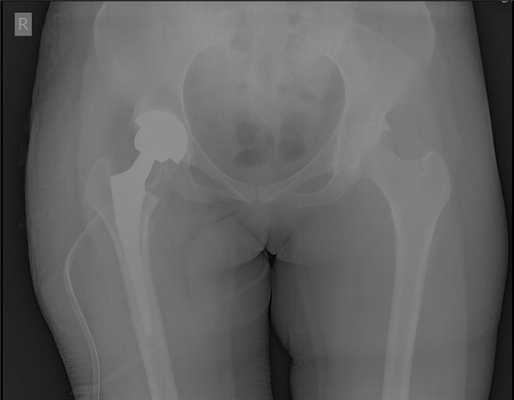

Выполнено тотальное эндопротезирование правого тазобедренного сустава эндопротезом фирмы Zimmer бесцементной фиксации, пара трения керамика\полиэтилен. Гладкое течение послеоперационного периода.

Рентгеногграммы после операции, положение компонентов эндопротеза правильное. Пациент активизирован на следующий день после операции, обучен ходьбе с дополнительной опорой на ходунки. Вторые сутки после операции, пациент ходит по палате и коридору без посторонней помощи с дополнительной опорой на ходунки.

Пациент выписан на 4 сутки после операции в удовлетворительном состоянии. В настоящее время функция опоры и ходьбы полностью восстановлена, ходит без дополнительной опоры, боли не беспокоят, восстановился нормальный стереотип походки.

Снимки после операции. Длина конечности восстановлена. В сравнении со снимками до операции хорошо видно как восстановилось нормальное положение тазового кольца и поясничного отдела позвоночника. Пациентка была прооперирована в день поступления, переведена из РАО через 2 часа после операции, активизирована через 6 часов после операции. На вторые сутки обучена ходьбе с дополнительной опорой на костыли.